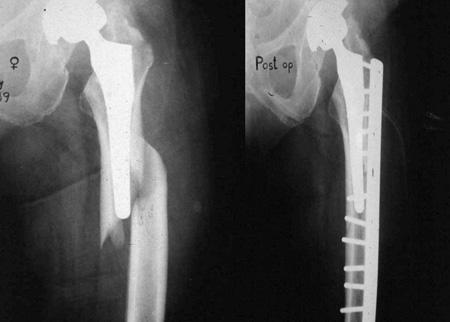

수술중 골절의 위치가 어디냐에따라 A,B,C 로 나뉘어지고 cortical 을 범하는지, nondisplaced 인지, unstable 인지에 따라서 1,2,3 으로 등급을 정합니다. 불안전성이 높거나 B이상부터는 거의 재치환술이 필요하다고 생각하면 쉽게 이해할 수 있을 것 같습니다.

일상생활을 하다가 부러진 경우에도 똑같은 Vancouver Classification 을 사용합니다. 수술중과 큰 차이는 위치에 따라 골절을 나뉘고 B만 구체적으로 나누고 나머지는 그냥 A,C로 골절을 나뉩니다. STEM 이 헐거운 경우 B2, STEM 바로 아래는 B1, 삽입물 주변의 골절 또는 뼈가 부족한경우 B3로 이해하면 됩니다.